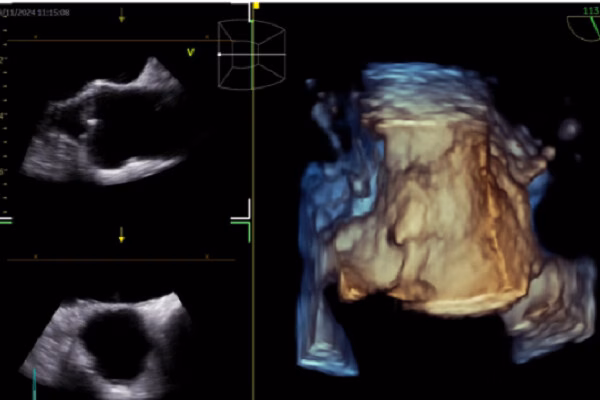

Trong siêu âm tim, AI giúp nhận diện cấu trúc cơ tim, đo đạc tự động và hỗ trợ báo cáo và chẩn đoán. Điều này giúp giảm thiểu sai sót và nâng cao độ chính xác của các kết quả chẩn đoán. AI cũng được sử dụng trong CT tim để cải thiện chất lượng hình ảnh, giảm liều xạ và cải thiện dự báo kết cục. Việc ứng dụng AI trong hình ảnh học tim mạch đã mang lại nhiều kết quả tích cực và hứa hẹn sẽ tiếp tục phát triển trong tương lai.